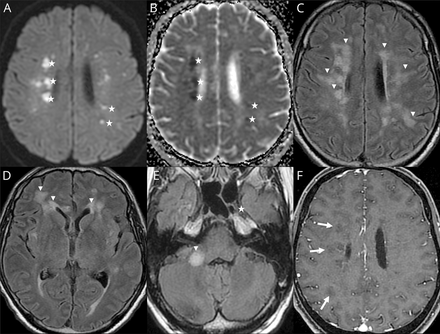

Ischemic strokes (27%) (figure e-1, available from Dryad,doi.org/10.5061/dryad.w9ghx3fm7), LME (17%) (figure 1), and encephalitis (13%) (figures 2and3and figure e-2, available from Dryad) were the most frequent neuroimaging findings. LME was seen on both postcontrast T1-weighted and FLAIR sequences and was even better visualized when delayed postcontrast FLAIR was performed. These signal abnormalities were not present on precontrast T1 or FLAIR images.

(A, B, D) Axial fluid-attenuated inversion recovery (FLAIR) and (C) diffusion-weighted MRIs. (A) Man 56 years of age: left hippocampus and amygdala FLAIR hyperintensity. (B) Woman 71 years of age: periventricular and subcortical white matter FLAIR confluent hyperintensities. (C) Man 55 years of age: corpus callosum splenium diffusion hyperintensity. (D) Man 64 years of age: FLAIR middle cerebellar peduncle hyperintensity.

Among the 8 encephalitis, 2 cases of limbic encephalitis, 2 cases of radiologic acute hemorrhagic necrotizing encephalopathy, 2 cases of miscellaneous encephalitis, 1 case of radiologic ADEM, and 1 case of CLOCC were described.